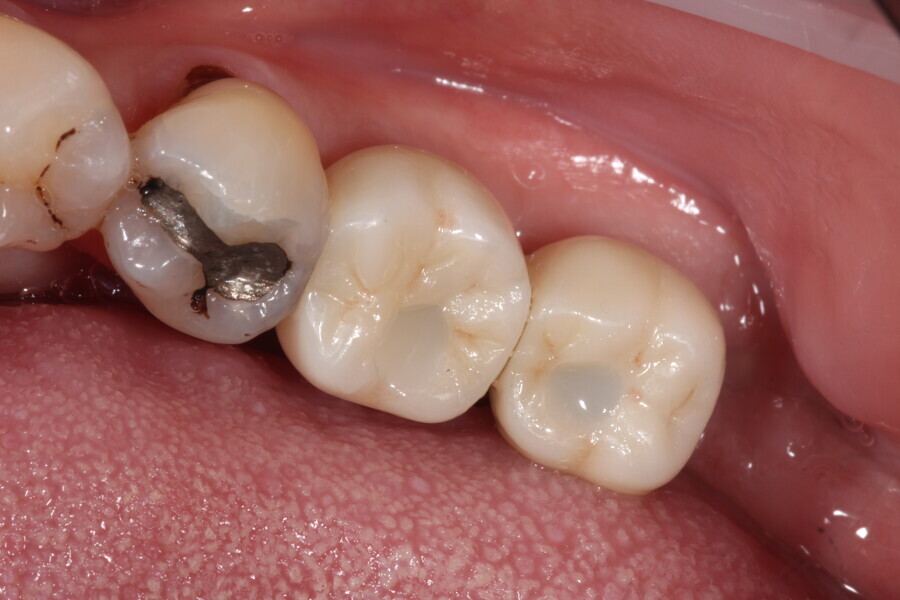

Fig. 9: Surgical placement of LL67 implants.